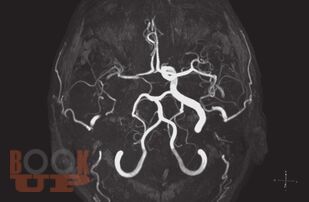

Настоящая брошюра, посвященная многозначному представлению о дисциркуляторной энцефалопатии, расшифровывает эту формулировку и позволяет более точно и осознанно оценивать подобных больных, а значит, и проводить им адекватное лечение. Наиболее детально здесь рассматривается атеросклероз мозговых артерий с его признаками на магнитно-резонансных и позитронно-эмиссионных томограммах, а также анализируется характерный для этой патологии липидный состав крови.